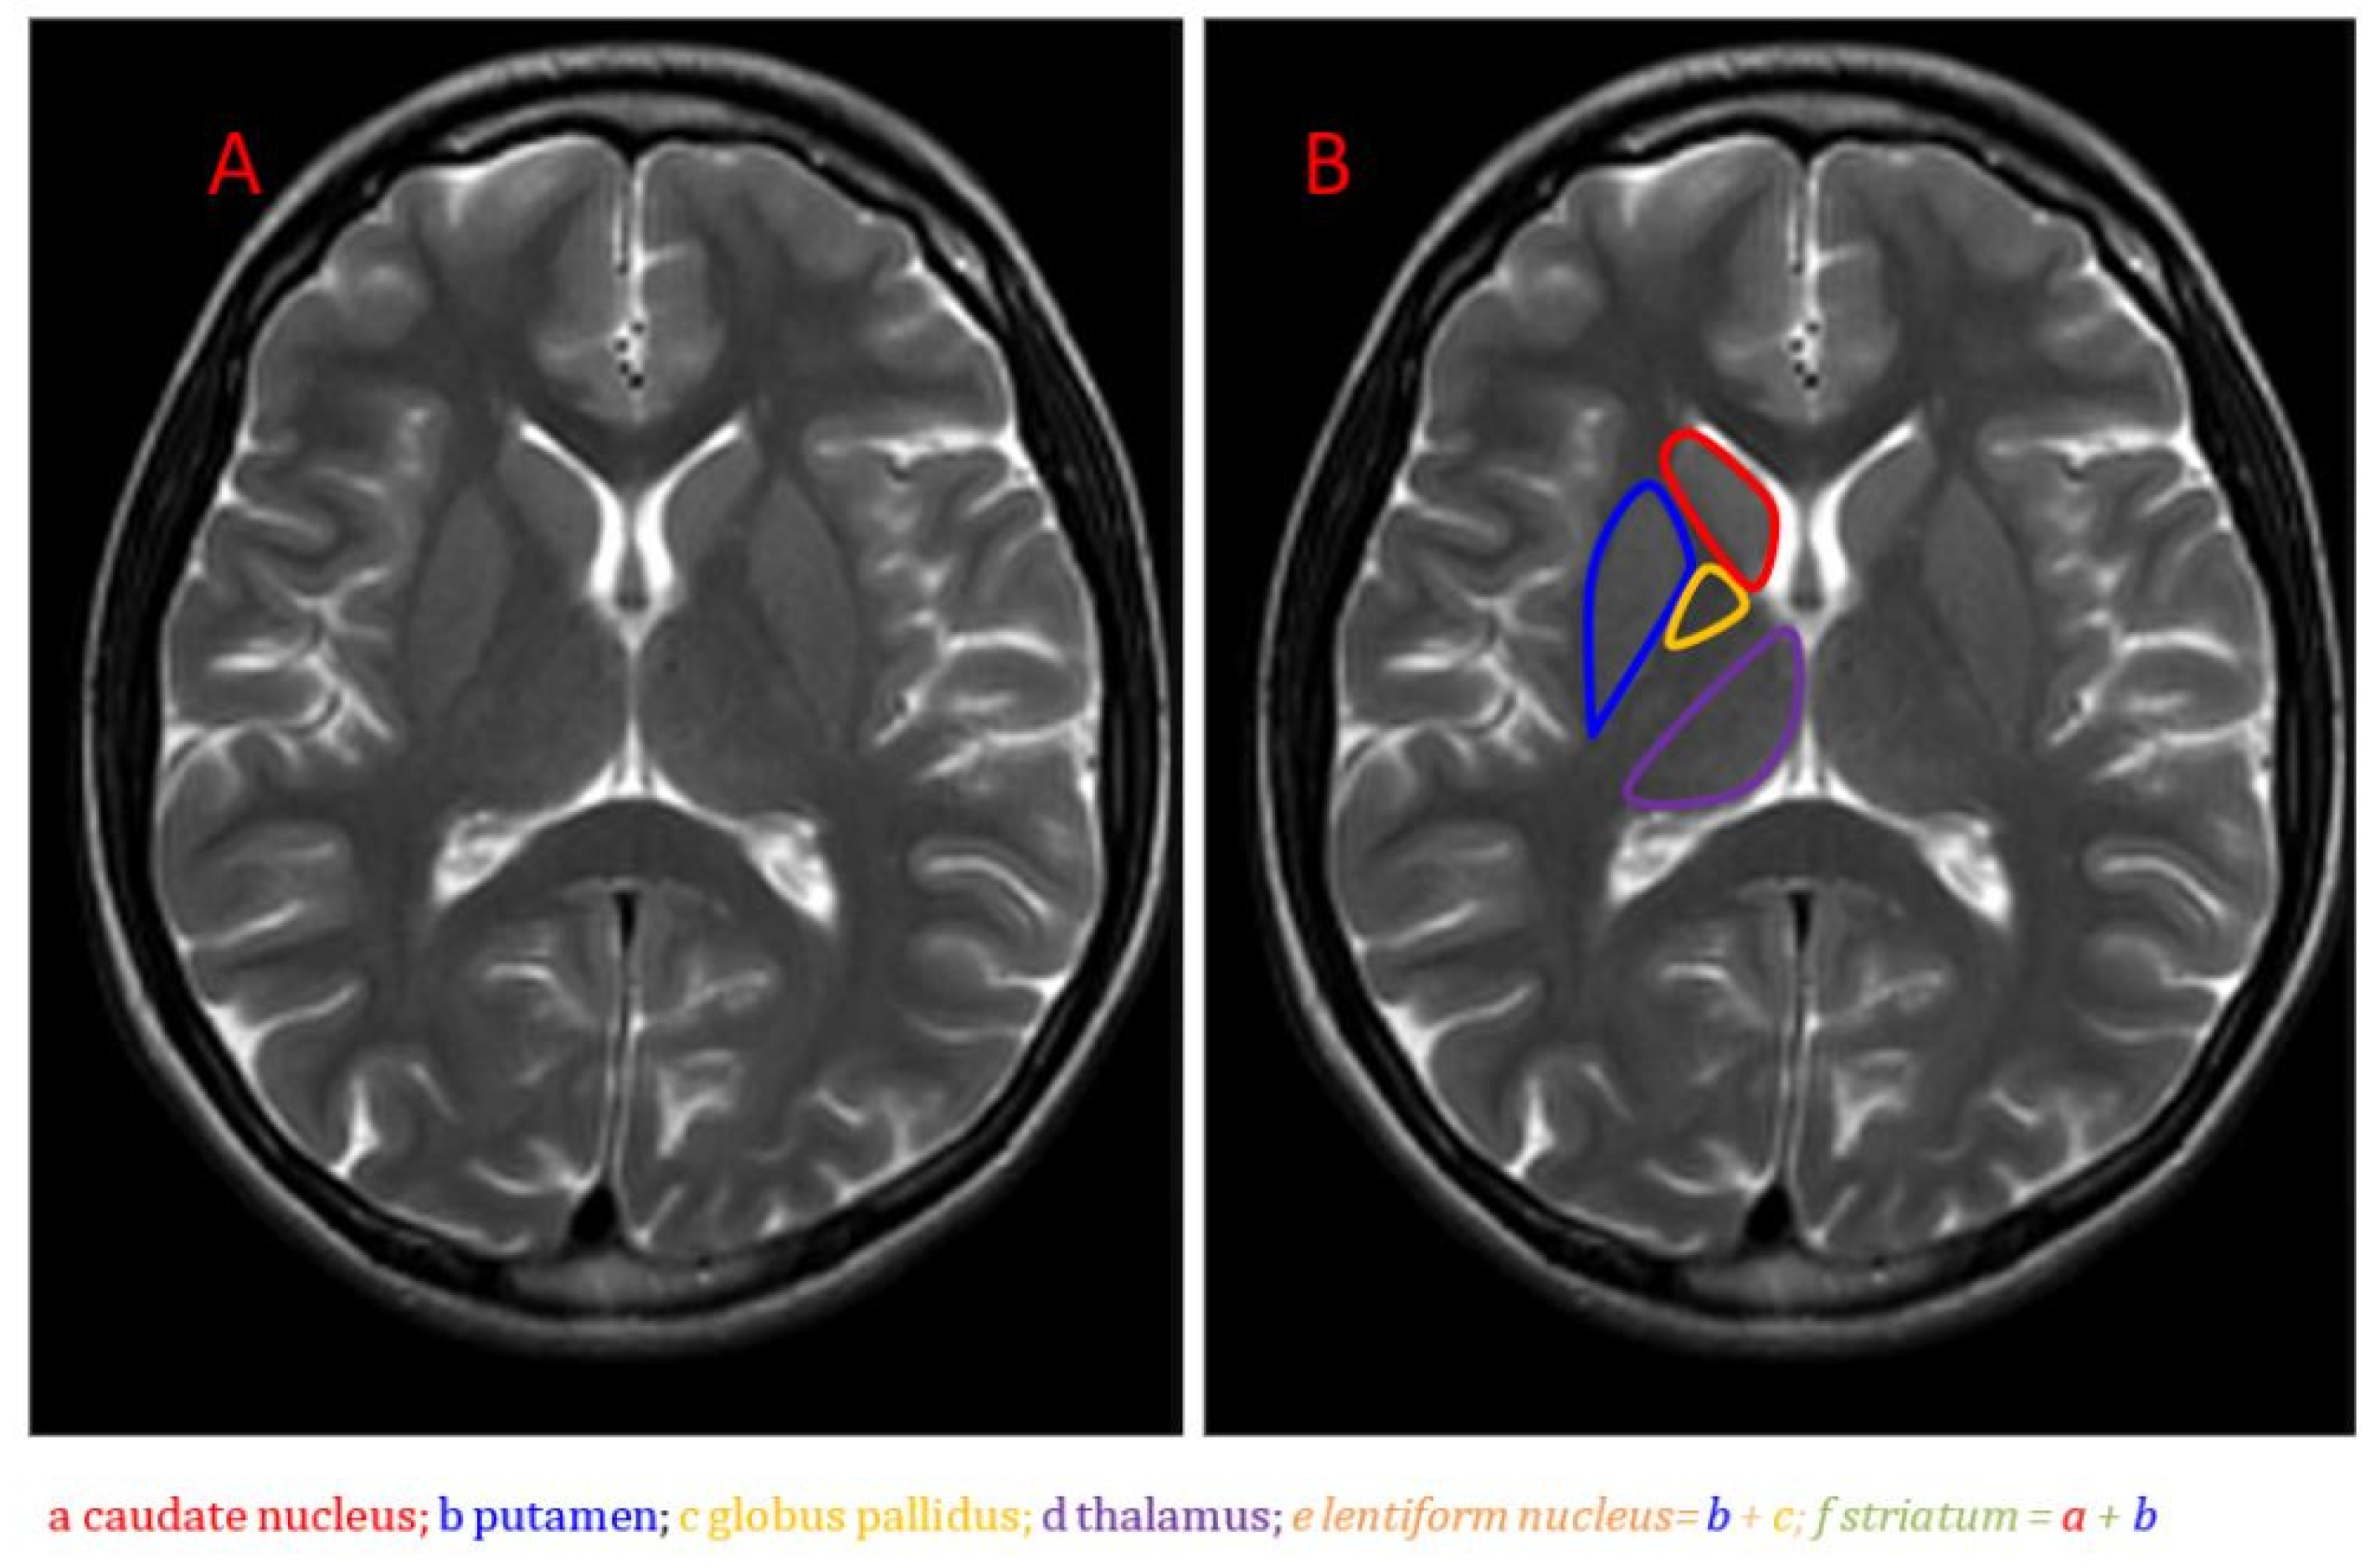

2. Basal Ganglia Dysfunction in Long-COVID Fatigue: Evidence from Neuroimaging

2.3. Mismatch in Structural Architecture

| Reference | Subjects | Disease Duration | Comorbidities | Hospitalization | Observed Brain Changes |

|---|---|---|---|---|---|

| Douaud et al., [10] | 600+ SARS-CoV-2 infected | Not specified | Cognitive impairment | Not specified | Connectivity weakening between basal ganglia, thalami, and sensory regions |

| Lu et al., [12] | Long-COVID patients vs. controls | 10 months | Hypertension, memory loss, headache, tremor, impaired mobility, myalgia | Hospitalized | Striatal neuroinflammation compromised neuronal integrity in caudate and putamen |

| Kandemirli et al., [14] | ICU COVID-19 patients | Not specified | Hypertension, diabetes mellitus, cerebrovascular accident, chronic kidney disease, coronary artery disease | In ICU | 56% had basal ganglia hyperintensities, reduced NAA/Cr and NAA/Cho ratios |

| Helms et al., [13] | 58 Severe COVID-19 patients | Not specified | Confusion, cognitive dysfunction | Hospitalized | Basal ganglia hyperintensities (MRI) |

| Hampshire et al., [18] | Recovered COVID-19 patients | Not specified | Anxiety, depression, lung conditions, psychiatric conditions | Hospitalized | Cognitive deficits linked to disrupted basal ganglia communication |

| Meinhardt et al., [19] | 33 deceased COVID-19 patients | Not specified | Not specified | Not specified | Olfactory SARS-CoV-2 invasion as path to central nervous system |

| Zhou et al., [20] | Recovered COVID-19 patients | Nearly 1 year | Diabetes, hypertension, hyperlipidemia | Hospitalized 17.5–41.5 days | Reduced white matter integrity in nigrostriatal pathways |

| Hafiz et al., [21] | 46 COVID-19 vs. 30 controls | 2 weeks post-discharge | Fatigue | Hospitalized | Higher gray matter volume in limbic regions and basal ganglia; correlation with fatigue |

| Heine et al., [22] | 50 long-COVID vs. 47 controls | Median 7.5 months | Anxiety, depression, sleep problems in long-COVID | 13% Hospitalized | Thalamus and basal ganglia volume loss, surface deformations, altered diffusion; correlated with fatigue |

| Deters et al., [23] | 33 mild COVID-19 patients | <6 months (n = 18) vs. >6 months (n = 15) | Persistent fatigue in some >6 month patients | Not hospitalized | Smaller putamen, pallidum, thalamus volumes in >6 month group, especially fatigued; frontal hypometabolism |

| Luo et al., [17] | 32 post-COVID-19 patients (16 fatigued, 16 non-fatigued) | 6.9 ± 4.8 months (FT), 8.5 ± 5.7 months (NF) | Not specified | Not hospitalized | Decreased globus pallidus activity in both fatigued and non-fatigued groups compared to healthy controls; non-fatigued group showed greater hypometabolism; right hemisphere more affected in both groups |